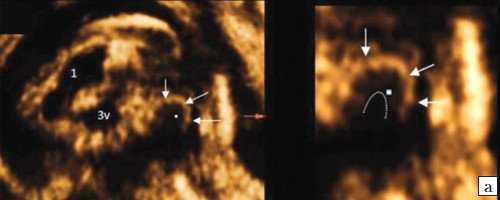

Анализ сохраненных трехмерных изображений позволил получить более детальные характеристики структур мозга плодов с РЭС. На среднесагиттальном срезе в наблюдениях 1, 2 и 4 (в наблюдении 3 получить качественно этот срез не удалось) отмечено наличие атипичной полукруглой формы шатра (fastigium) 4-го желудочка, гипоэхогенная структура мозжечка с контрастирующим наружным контуром (рис. 3). При этом в первых трех наблюдениях отмечено полное отсутствие структур червя, тогда как в наблюдении 4 по контуру 4-го желудочка выявлены гиперэхогенные структуры, расцененные как передние отделы червя. Наличие передних отделов червя отражает и ряд послойных срезов в режиме TUI (рис. 4). У плода в наблюдении 4 также обращает на себя внимание относительное расширение надмозжечковой цистерны, с линейными структурами, при нормальной ориентации намета мозжечка (рис. 4).

а) Наблюдение 2, 3D. На эхограмме: 1 - боковой желудочек, 3v - 3-й желудочек, стрелки - контур мозжечка, пунктирная линия - шатер.

б) Наблюдение 4. На эхограмме: М - мозжечок.

На эхограмме: М - мозжечок, 4v - четвертый желудочек, короткие стрелки - фрагменты червя.